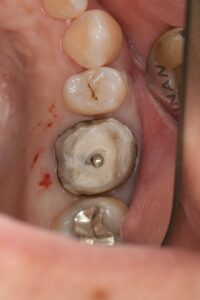

ⅰ.抜髄(過去に神経の治療がされていない歯の治療)の場合

➡むし歯の除去(隔壁作製)、神経の除去と根管内クリーニング、いけたら根管充填とレジンコア(土台)

ⅱ.再治療(過去に治療してる根管)の場合

➡過去の充填物やむし歯の除去と隔壁作製、根管内の充填物の除去とクリーニング